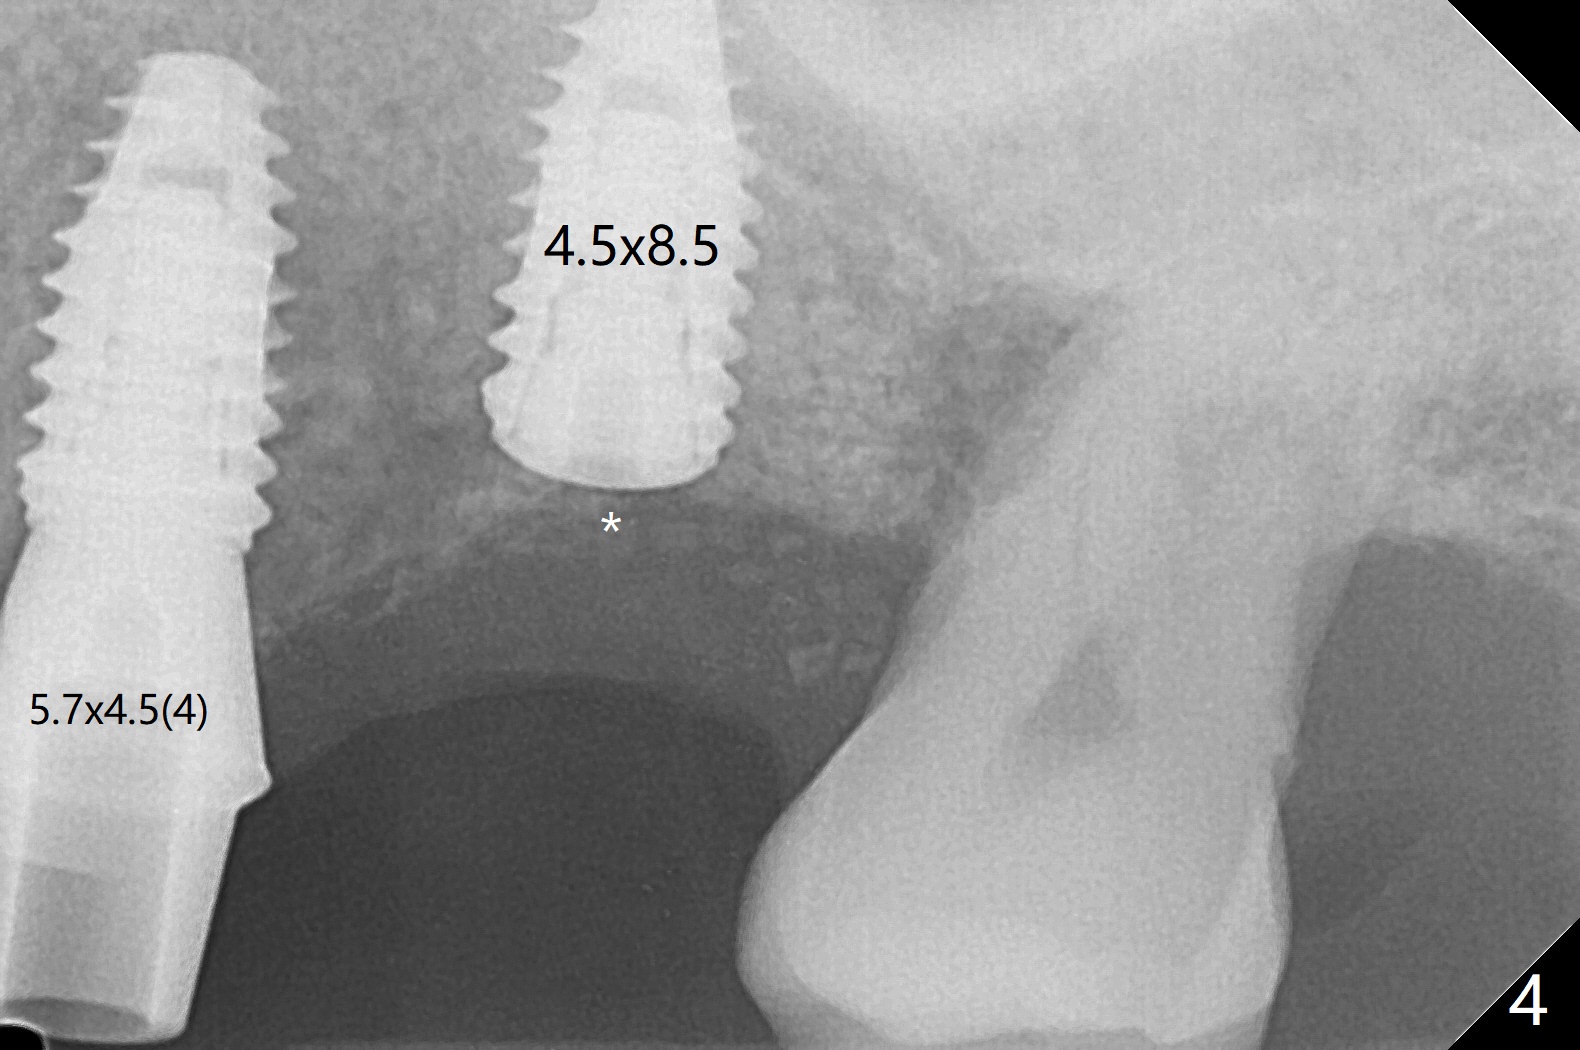

左上六植牙第三次失败后五个月,牙槽嵴宽度尚可,切开后放置导板,3.2乘19毫米园钻头好像接近上颌窦底板(图一),但是粘性骨块和4乘10毫米报废植体就不能进入上颌窦(图二),最后不得不使用3毫米Bicon骨凿,之后同一个报废植体就似乎进入上颌窦(图三),4.5乘8.5毫米正式植体植入深度和稳定性均正常(图四),腭侧植体稍微暴露,放置愈合螺丝后,放置骨粉和PRF膜,缝合,左上5植体放置5.7x4.5(4)毫米基台,固定牙周敷料。术后5.5个月植体好像整合(图五),缺牙间隙特别小,5临时牙冠(P)必须取出才能切开暴露植体,放置5.5x5毫米愈合基台(图六)。伤口愈合后,必须做渐进性负荷,之后做简单局部矫正,推7往远中,6缺失3年,7往近中倾斜移位。两周后牙周敷料脱落,伤口愈合,放置修复基台,故意将基台平面朝远中,足够空间制作临时牙冠(图七)。调整基台长度(比较图七,八)。制作连体牙冠(5,6),有意提高5牙冠高度,使左上7不与对合牙接触,有利于远中移位(图九)。也要在对侧提高咬合(图十)。局部矫正一个月后,磨去右侧咬合垫和磨短左上5,6临时牙冠,前牙还不能完全接触(图十一)。1-2星期前牙开合自行消失,取模做左上5,6牙冠。局部矫正似乎使左上7远中移位大约3毫米(比较图十二,十三)。粘固拧紧后(20 Ncm)14号牙牙冠咬合增高,拍摄根尖片(图十三),两个基台好像仍然完全就位,然后调整咬合。